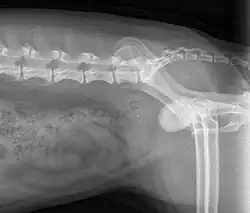

X-Ray

An example of an X-ray from a dog.

A form of electromagnetic radiation used to examine internal structures such as bones, blood vessels and some organs. In veterinary medicine, restraint methods such as sand bags, tying, manual restraint, and medications are used to increase easy of restraint